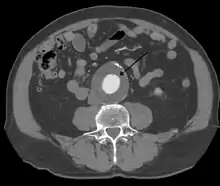

The diagnosis of an abdominal aortic aneurysm can be confirmed at the bedside by the use of ultrasound. Rupture may be indicated by the presence of free fluid in the abdomen. A contrast-enhanced abdominal CT scan is the best test to diagnose an AAA and guide treatment options.

A rapidly expanding aneurysm should under normal circumstances be operated on as soon as feasible, as it has a greater chance of rupture. Slowly expanding aortic aneurysms may be followed by routine diagnostic testing (i.e.: CT scan or ultrasound imaging).

For abdominal aneurysms, the current treatment guidelines for abdominal aortic aneurysms suggest elective surgical repair when the diameter of the aneurysm is greater than 5 cm (2 in). However, recent data on patients aged 60–76 suggest medical management for abdominal aneurysms with a diameter of less than 5.5 cm (2 in).[11]